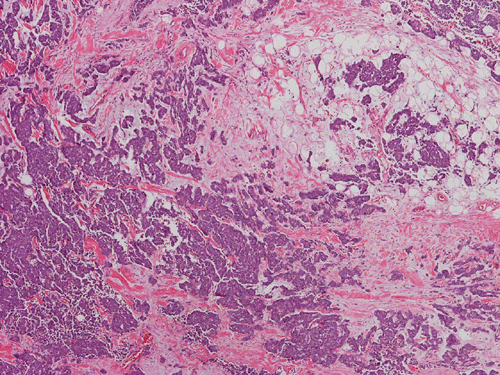

The mass appears to be a subcutaneous tumor that spares the dermis and epidermis (Panel A). On scanning magnification, the tumor has a infiltrative growth pattern (Panel B). Intrestingly, the tumor does not really invade into the parotid gland (Panel C). On medium magnification, the tumor cells arrange in irregular islands with a solid pattern (Panel D). On high magnification, the tumor cells have medium sized large nuclei with high nuclear to cytoplasmic ratio (Panel E) and scant amount of cytoplasm. The cytoplasmic membrane is not distinct. The nuclei have a coarse salt and pepper like pattern and without prominent nucleoli. On immunohistochemistry, strongly positive expression of CK20 in terms of dots are present in many of the tumor cells (Panel F). A similar but stronger staining pattern with antibodies against neurofilament proteins (Panel G).  The tumor cells are also positive for synaptophysin (Panel H).

Histologically, MCC is a dermal based tumor. Histological features often typify that of small, round blue cell tumors. The cells have very high nuclear cytpplasmic ratio, hyperchromatic nuclei with evenly distributed chromatin without prominent nucleoli. Mitotic figures are common. The tumor is characteristically separated from the epidermis by a "grenz" zone. It can be morpholgoically classified into three subtypes, namely the small cell type, the trabecular type and the intermediate type.

The small cell type have features of a small blue turmor with scant cytoplasm and small to medium sized nuclei with salt and pepper chromatin. There are numerous mitosis and scattered pyknotic nuclei. This tumor often expands into the subcutaneous tissue. The small cell type is similar to small cell tumors found at other sites. It also arises in the dermis as solid sheets and cells clusters.  The clinical behavior tends to mirror that of small cell tumors of other origin. The least common subtype is the trabecular type, in which the cells are arranged into organoid clusters and trabeculae with ribbons.  It often occurs adjacent to adnexal structures. The cells tend to contain more cytoplasm. The intermediate subtype is most frequently seen. It has a solid and diffuse growth pattern.  Cells are less compact and contain less cytoplasm than the trabecular subtype and they usually arise adjacent to adnexa, although it can invade the epidermis.  Typically they are mitotically active and necrosis is not uncommon. It has a more aggressive clinical behavior than the trabecular subtype.